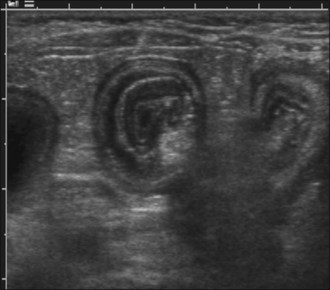

Survey abdominal radiographic findings may be suspicious for intussusception and positive contrast studies are often diagnostic. However, in experienced hands abdominal ultrasonography is the preferred method of diagnosis. A target-like mass consisting of multiple hyperechoic and hypoechoic concentric rings in transverse section (Figure 29.8), or the appearance of multiple hyperechoic and hypoechoic parallel lines in longitudinal section, is considered virtually diagnostic of an intussusception.

Figure 29.8 Target-like ultrasonographic appearance of intussusception in transverse section.

(Photograph courtesy of Andrew Parry)